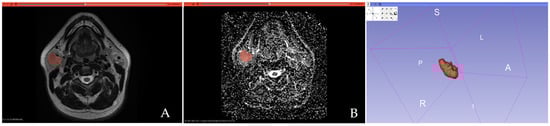

2.3. Tumor Segmentation